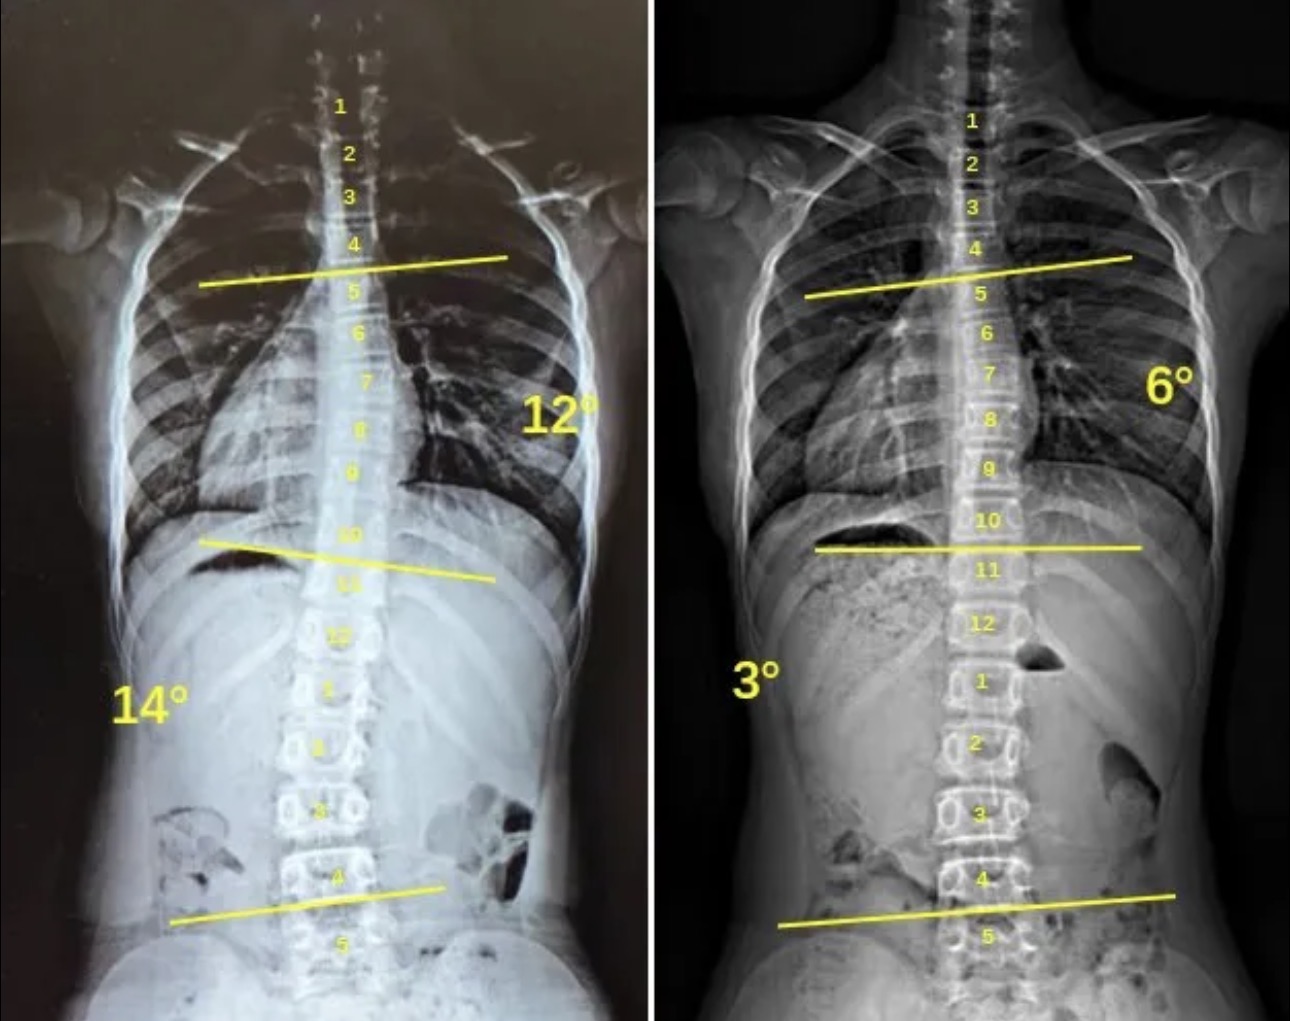

衷德脊柱,我们只关注侧弯保守治疗~

Zhongde Spine, bending no breaking ~